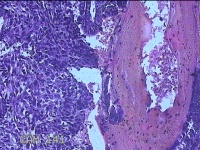

宫腔内容物

性别

女

年龄

43岁

临床诊断

异常子宫出血

一般病史

月经不规则2年余,发现宫颈赘生近1年,宫颈外科可见多个赘生物。

标本名称

大体所见

纱布一块,内有灰白暗红色不规则碎组织1.8x1.3x0.3cm一堆。